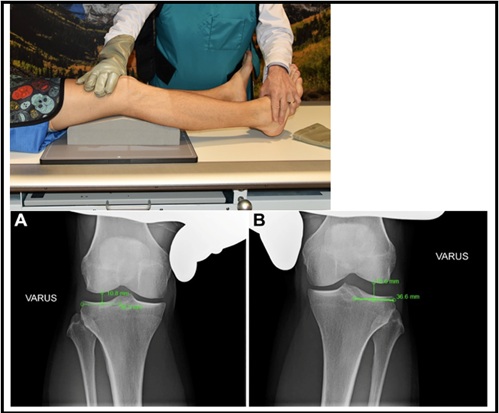

Bilateral varus stress radiographs are also be helpful in evaluating for PLC injury. To generate this view—the patient is supine, and an angled foam block is inserted underneath the knee to obtain a standard 20 degrees of knee flexion. Then, the clinician applies a maximum varus force by placing one hand on the medial femoral condyle and one hand on the lateral aspect of the foot, and an image is taken. This is repeated on the non-injured leg, and the side to side difference (SSD) in lateral compartment gapping is calculated. Of note, it is imperative the physician provides an equal varus force to each leg to obtain an accurate result. A previous cadaveric study determined that a side to side difference > 2.7 mm to be indicative of an isolated, grade III PLC injury, and a SSD > 4 mm is indicative of a complete PLC injury17. This was considered to be the gold standard for side to side difference. However, new evidence in patients has shown that a SSD of > 2.2 mm to be indicative of a grade III FCL tear 18. The SSD is calculated as follows: the distance from the most lateral aspect of the lateral tibial plateau to the lateral tibial eminence is measured. At the midpoint of this line, a line is drawn perpendicularly towards the femoral condyle. The length of the perpendicular line is the SSD and is depicted in figure 518.

Figure 5: Varus Stress Radiographs (A: non-injured/B with combined ACL and PLC Injury18)